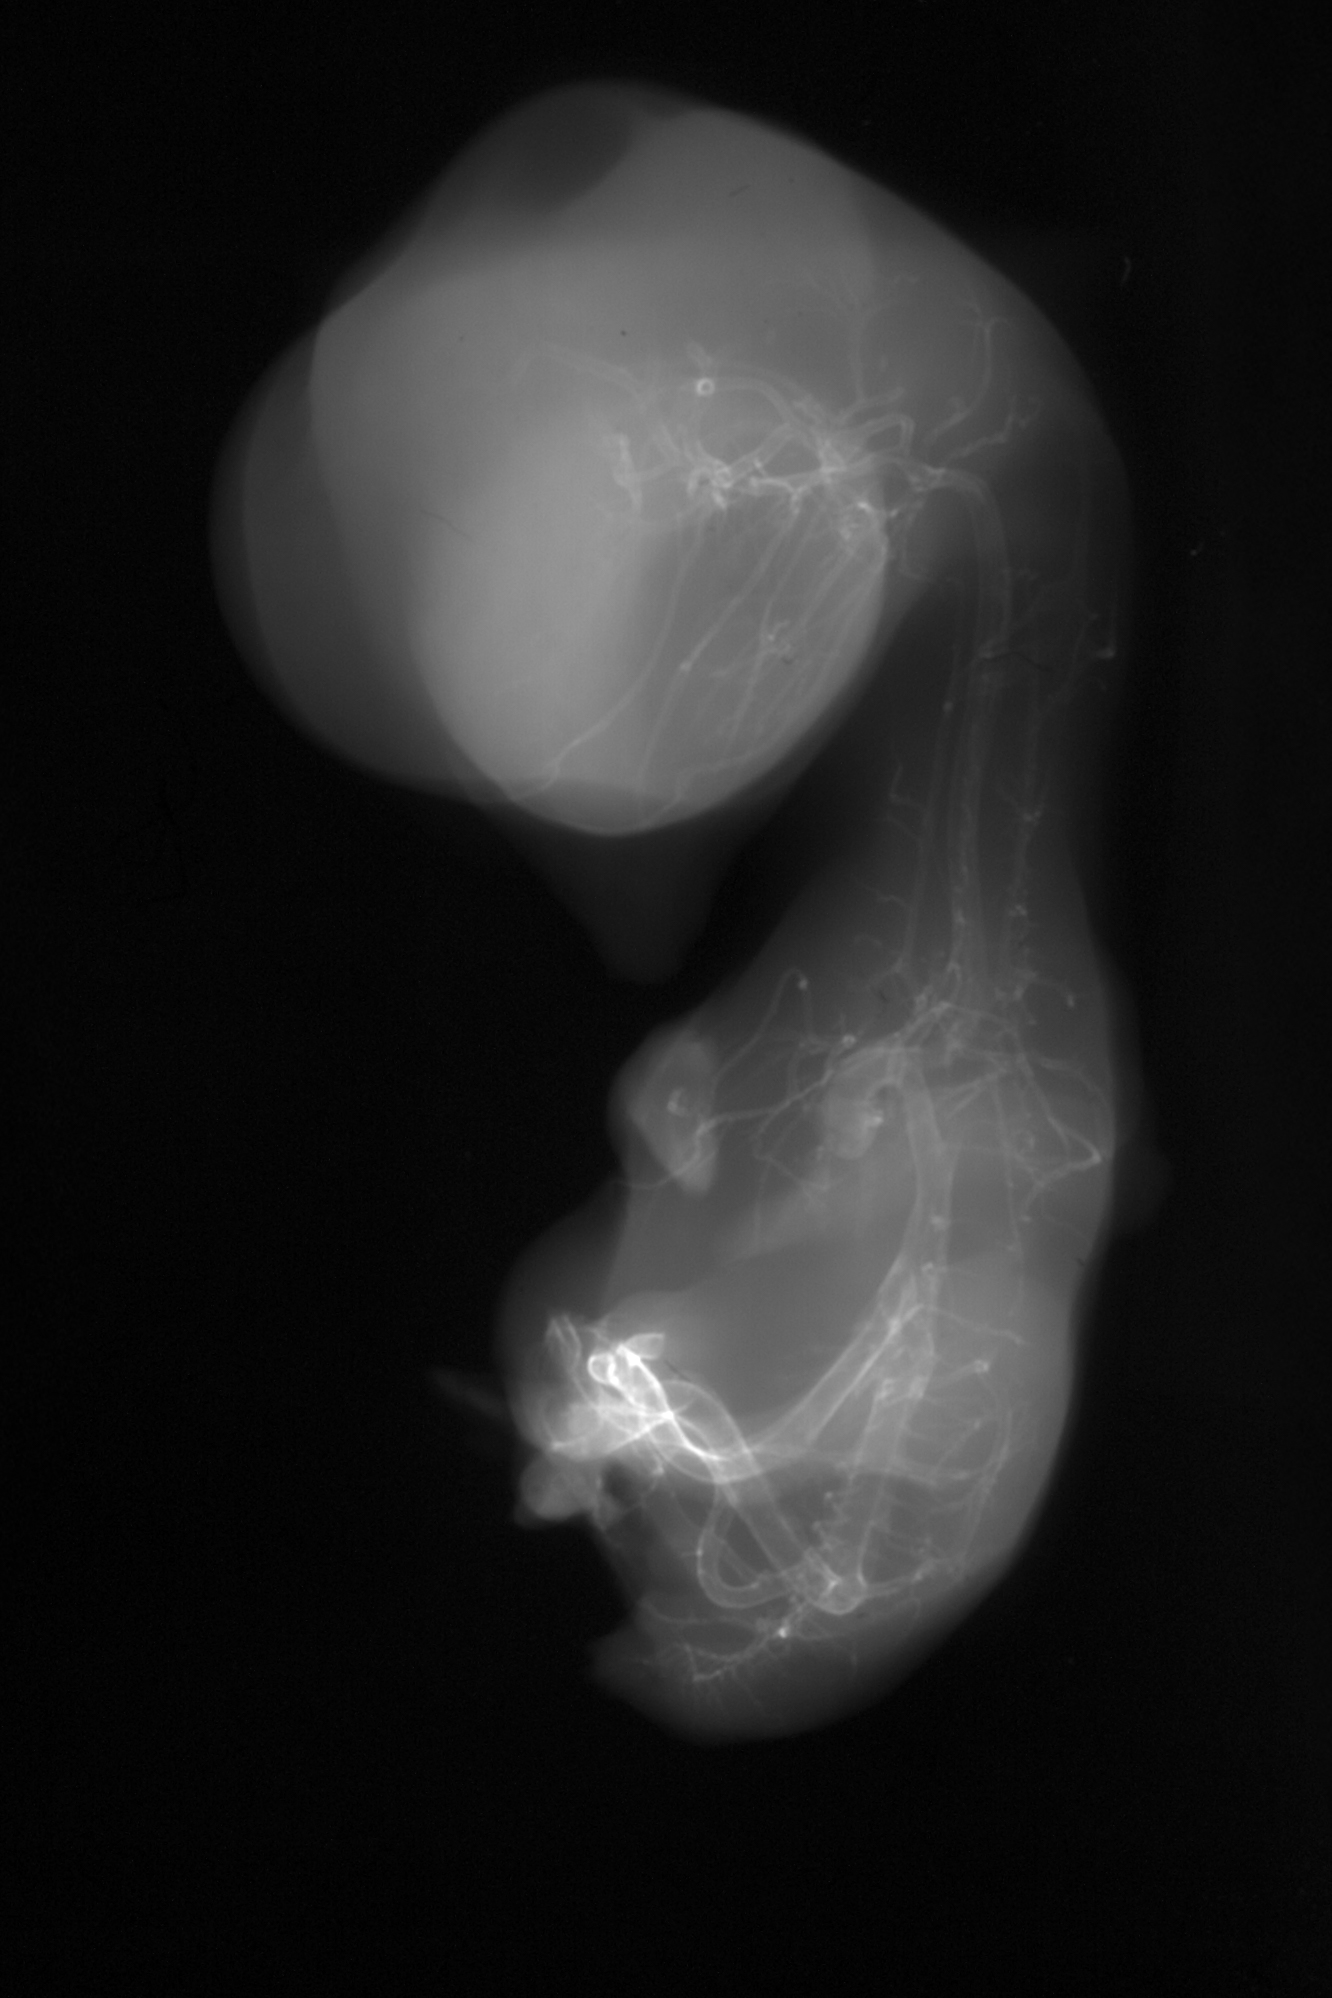

Chick Embryo Microangiography

Hamburger-Hamilton (HH) Stage 35 (approx. 8.5 - 9 days)

X-Ray Micrographs